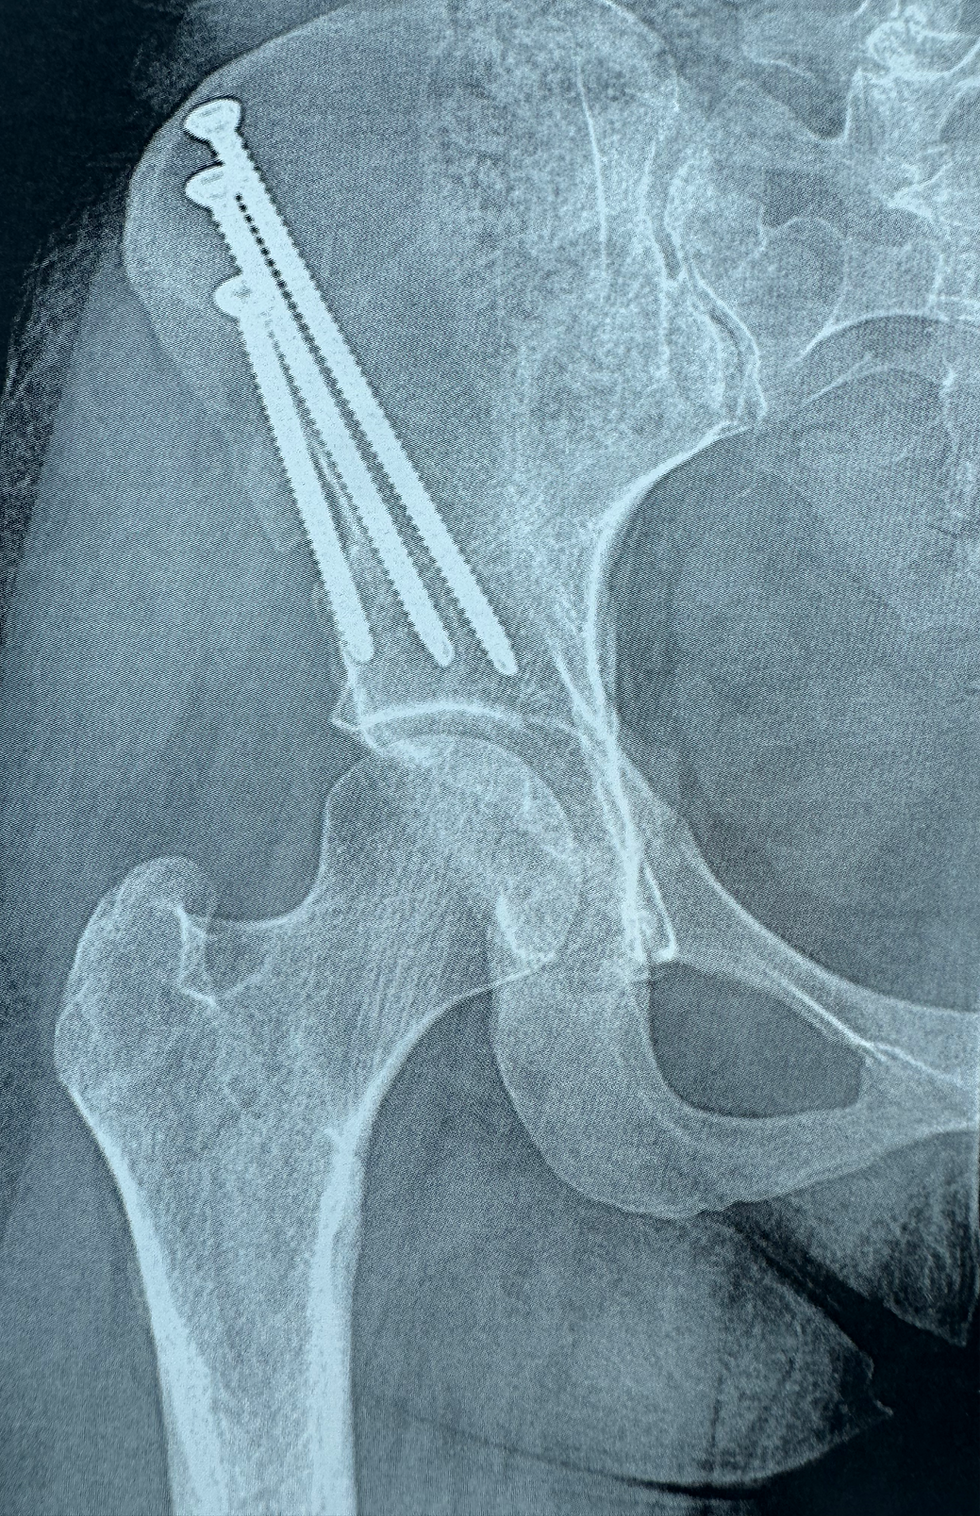

Radiografías (X-rays): miden la cobertura y alineación del acetábulo.

Osteotomía Periacetabular (PAO)

El procedimiento de referencia para la displasia de cadera en adultos. La cirugía reposiciona el acetábulo para que cubra mejor la cabeza femoral.

Mejora la estabilidad articular.

Protege el cartílago y el labrum.

Puede retrasar o prevenir la artritis.

Ideal en pacientes jóvenes con superficies articulares preservadas.